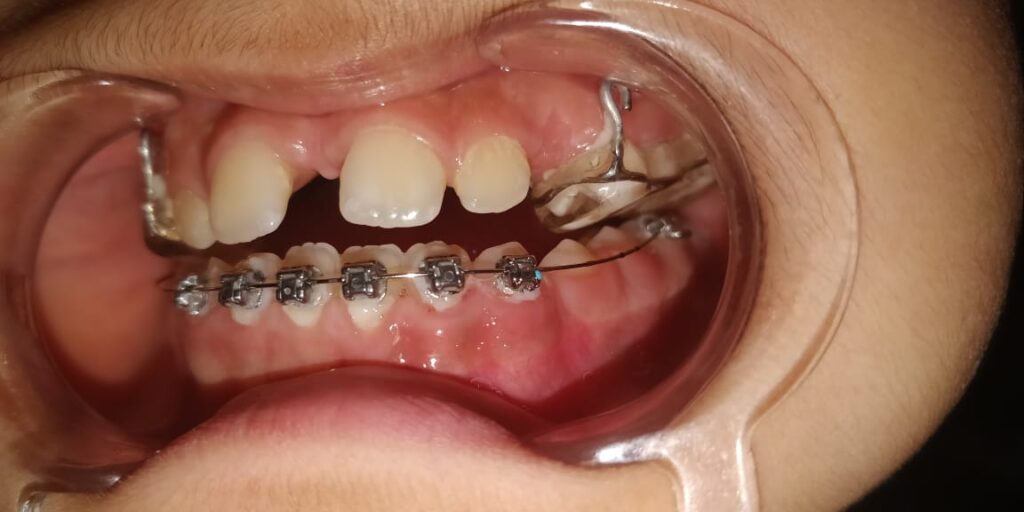

63) Taim – Class 3 skeletal pattern with anterior crossbite. – Plan – To get point A forward , followed by facemask and then lower 2×4 appliance – Phase 1